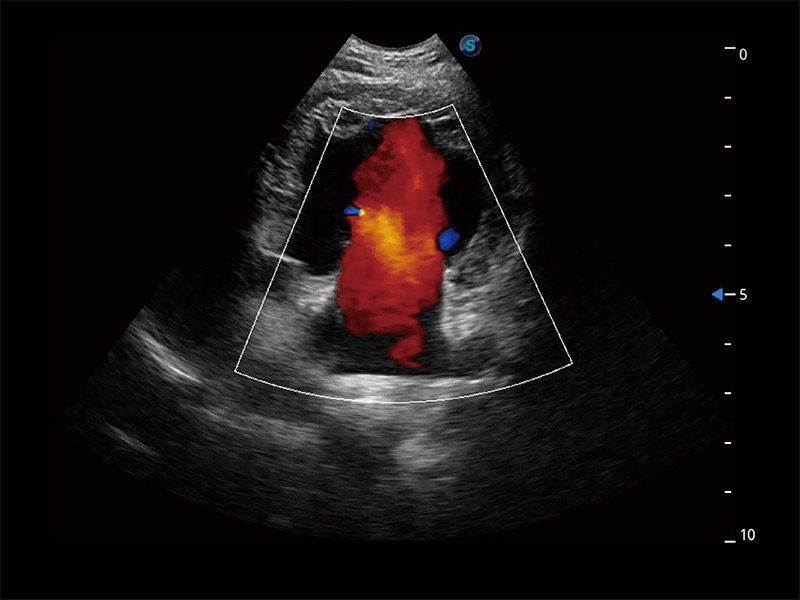

在傳統(tǒng)二維血流成像的基礎(chǔ)上,呈現(xiàn)血流的立體感,具有動(dòng)感的生命力之美。即便是微小的血管也能輕松應(yīng)對(duì),提高了血流的視覺敏感性。